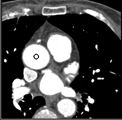

Samples for ascending aorta detection (black circle):

Cluster of candidate points in the ascending aorta.